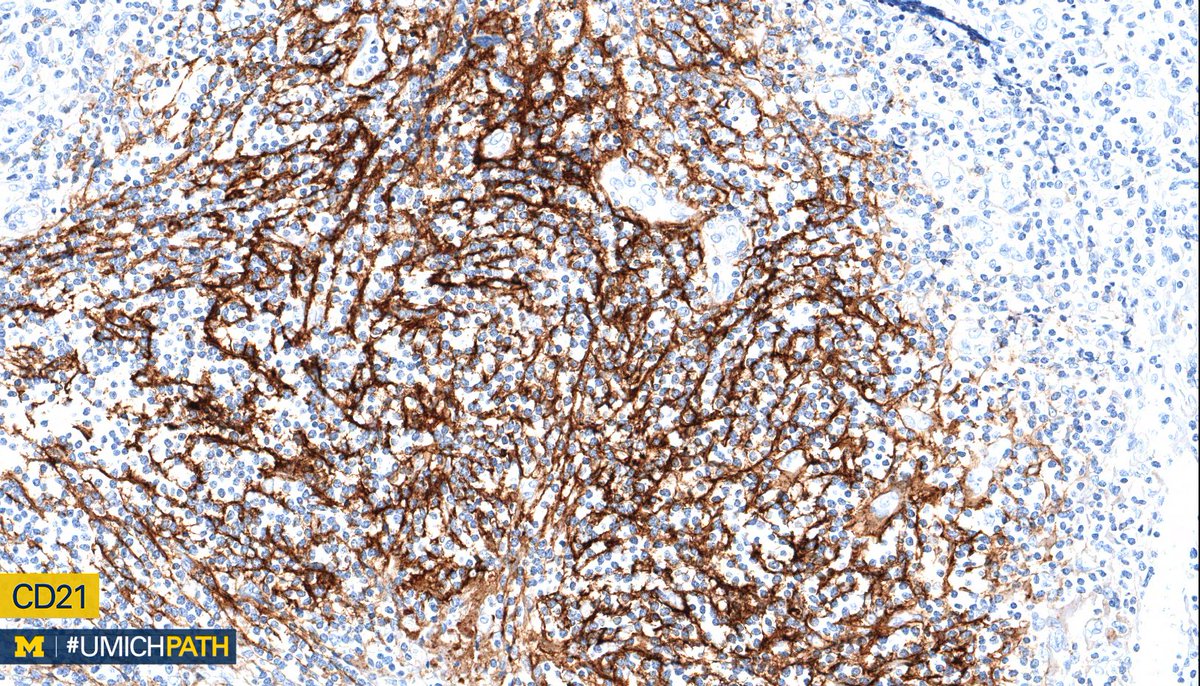

2015 july 3, luis f. J cancer res immunooncol 5: Angioimmunoblastic t cell lymphoma (aitl) presents in older patients and the median age at diagnosis is approximately 60. In aitl, the tumor cells are often accompanied by a mixed inflammatory infiltrate. Angioimmunoblastic lymphadenopathy (aild) with dysproteinemia;

Angioimmunoblastic t cell lymphoma (aitl) is a peripheral t cell lymphoma characterized by systemic disease, a polymorphous infiltrate involving lymph nodes, and a prominent proliferation of.

I'll post short song preview soon. Angioimmunoblastic t cell lymphoma (aitl) is a peripheral t cell lymphoma characterized by systemic disease, a polymorphous infiltrate involving lymph nodes, and a prominent proliferation of. Dr flora poon, victorian dermatology registrar, st. (pathology) relating to, or characterised by immunoblasts of lymph glands. Learn more about angioimmunoblastic lymphadenopathy from related diseases, pathways, genes and ptms with the submit your blog on angioimmunoblastic lymphadenopathy to be featured! Angioimmunoblastic t cell lymphoma microenvironment. Blood diseases, cancer diseases, immune diseases, rare diseases. In this image, there are scattered eosinophils present. 1 department of hematology, iuliu hatieganu university of medicine & pharmacy. J cancer res immunooncol 5: 2015 july 3, luis f. Angioimmunoblastic — an·gio·im·mu·no·blas·tic (an″je o im″u no blasґtik) characterized by the presence of immunoblasts (lymphoblasts) and an inflammatory infiltrate in small blood vessels. Amira m elbendary, mbbch, msc;

In aitl, the tumor cells are often accompanied by a mixed inflammatory infiltrate. Blood diseases, cancer diseases, immune diseases, rare diseases. Angioimmunoblastic t cell lymphoma microenvironment. 2015 july 3, luis f. Angioimmunoblastic lymphadenopathy (aild) with dysproteinemia;